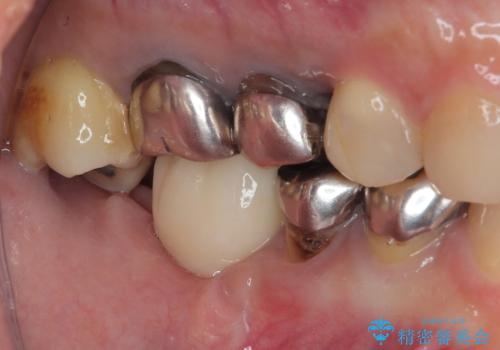

- 「歯を抜いたので、インプラントを入れてほしい」という主訴で来院された患者様です。

他院で歯根破折により抜歯をしたとのことでした。

CTにより残存骨量を確認しインプラント埋入を行っていくこととしました。

今後手前の根管治療を行っている歯が歯根破折を起こして抜歯になる可能性を想定して手前の歯に平行にインプラント埋入を行っています。